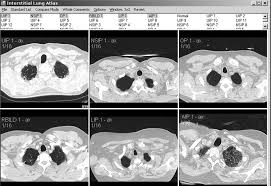

Interactive High Resolution Computed Tomography Digital Atlas Of Interstitial Lung Disease Academic Radiology